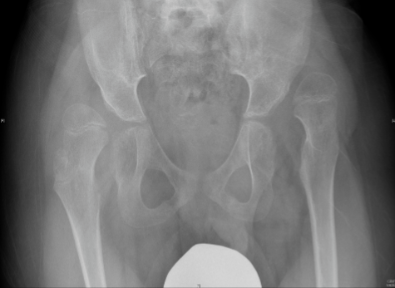

Σε παιδιά με εγκεφαλική παράλυση μεγίστης σημασίας είναι ο προ-συμπτωματικός έλεγχος για εξάρθρημα του ισχίου. To εξάρθρημα ισχίου είναι σύνηθες φαινόμενο σε άτομα με εγκεφαλική παράλυση, τα οποία είναι καθηλωμένα σε τροχοκάθισμα. Η πρόληψη της πάθησης είναι σημαντική για το λόγο ότι προλαμβάνει τον πόνο και σοβαρές παραμορφώσεις, όπως η σκολίωση. Σε πολλές χώρες στο εξωτερικό πραγματοποιείται προληπτικός έλεγχος ισχίων, με αποτέλεσμα τα ποσοστά εμφάνισης εκτοπισμού ισχίων να είναι στο ναδίρ. Για αυτό τον λόγο συνίσταται συστηματική κλινική εξέταση και ακτινογραφικός έλεγχος σε παιδιά με εγκεφαλική παράλυση, τα οποία είναι καθηλωμένα σε τροχοκάθισμα.

Για αποφυγή εμφάνισης εξάρθρωσης ισχίων ο γιατρός, ανάλογα με την κατάσταση του εκάστοτε ασθενούς, μπορεί να συστήσει συγκεκριμένες φυσιοθεραπείες ή ορθωτικά βοηθήματα, εκχύσεις βοτουλίνης ή χειρουργική επέμβαση για χαλάρωση των μαλακών μορίων. Όταν το εξάρθρημα της κεφαλής του μηριαίου ξεπερνά το 40% γίνεται χειρουργική επέμβαση με οστεοτομία μηριαίου και λεκάνης.

Οι εικόνες απεικονίζουν περιστατικό του Δρ. Ζένιου με εγκεφαλική παράλυση (non-walker), όπου παρουσιάστηκε με πόνο. Υποβλήθηκε σε χειρουργική επέμβαση για ανάταξη και των δύο ισχίων με οστεοτομία λεκάνης και μηριαίου.

Προ-εγχειρητικά